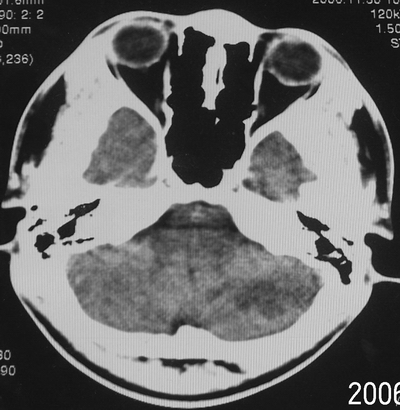

患者、男、18y,头痛5天入院。

左小脑、右丘脑区低密度影,无明显强化及占位表现,男18y,先考虑脑部炎性病变,如脑炎、血行播散性感染等,建议结合临床如脑脊液检验。

左侧小脑半球及右丘脑低密度影,考虑脑梗塞可能.

单独看左侧小脑半球的不规则形囊性低密度灶,从发病部位、年龄以及无强化、无占位效应的特点可以考虑毛细胞瘤型星形细胞瘤。同样,如果单独看右侧丘脑的近圆形低密度,也可以考虑囊变形星形细胞瘤。只是胶质细胞瘤一般为单发直接浸润、蔓延生长,而不是在脑内同时出现多个病灶,且瘤周没有一点儿水肿,暂时不予以考虑。

脑炎倒是首先可以考虑,只是临床症状、病史不很符合,建议狼兄仔细了解病史以及其他临床资料。

左侧小脑半球及右丘脑低密度影,考虑炎症可能性大

左侧小脑半球及右丘脑低密度影,考虑  1、脑梗塞灶. 2、占位性病变,建议作mri检查

支持右侧丘脑与左侧小脑梗塞,